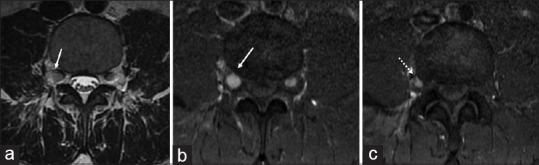

Human herpesviruses, particularly the varicella-zoster virus, are notorious for affecting the central nervous system, especially when secondarily reactivated from a latent state. We present one such case of zoster radiculitis with an ensemble of typical dermatological and neurological features diagnosed on imaging and cerebrospinal fluid (CSF) studies and encourage the consideration of viral (zoster) neuritis as a differential in patients presenting with radicular pain.

人类疱疹病毒,特别是水痘-带状疱疹病毒,以影响中枢神经系统而臭名昭著,尤其是从潜伏状态再次激活时。我们介绍了一例带状疱疹神经根炎病例,其具有典型的皮肤病学和神经病学特征,通过影像学和脑脊液(CSF)研究诊断,并鼓励在出现神经根痛的患者中考虑病毒性(带状疱疹)神经炎作为鉴别诊断。